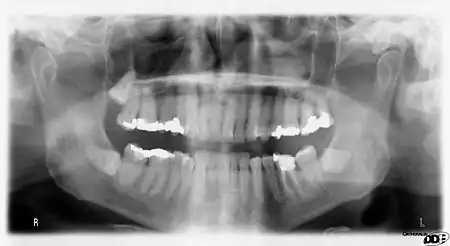

Usually, there are 20 primary ("baby") teeth and 32 permanent teeth, the last four being third molars or "wisdom teeth", each of which may or may not grow in. Among primary teeth, 10 usually are found in the maxilla (upper jaw) and the other 10 in the mandible (lower jaw). Among permanent teeth, 16 are found in the maxilla and the other 16 in the mandible. Each tooth has specific distinguishing features.